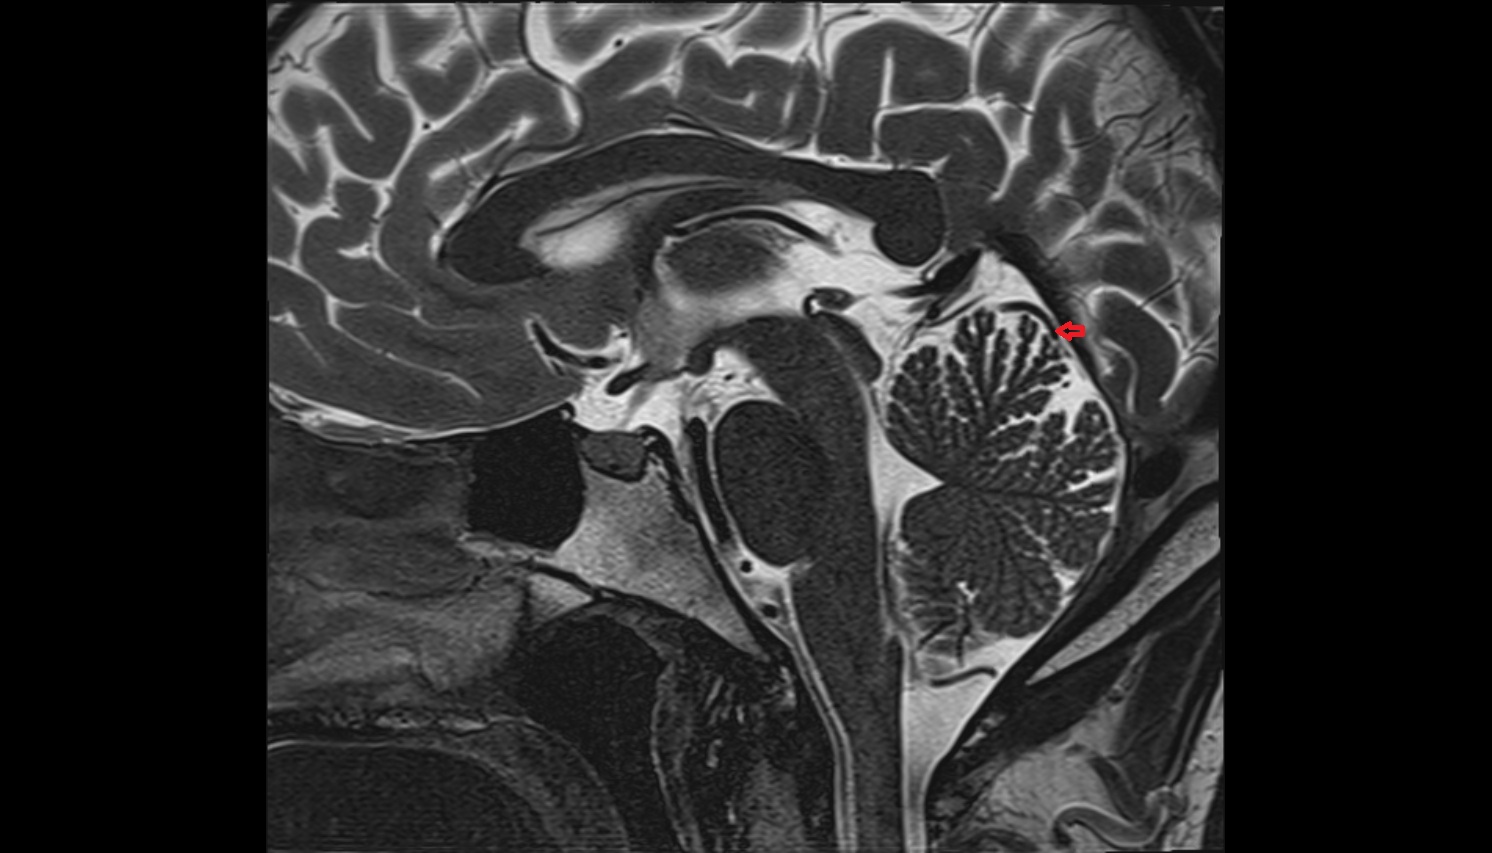

- Fetal brain

- Fetal cerebellum

- Fetal third ventricle

- Fetal fourth ventricle

- Fetal lateral ventricle